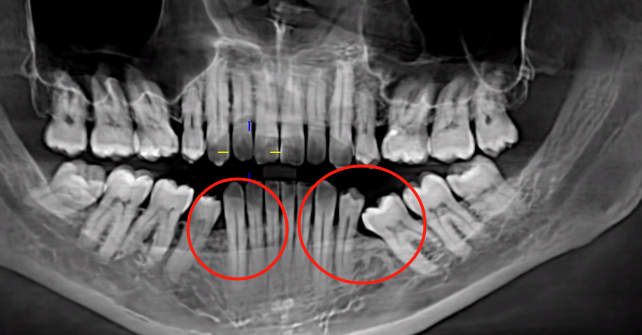

Another critical consequence is the mesial drift (tilting) of adjacent teeth into the edentulous space. Without the physical support of the missing tooth, the neighboring teeth lose their natural occlusal balance, causing them to shift gradually toward the gap. This drift weakens the periodontal ligament and alveolar bone support of the adjacent teeth, accelerating their degradation and reducing their lifespan. More importantly, severe tilting can obliterate the necessary three-dimensional space for implant placement (requiring at least 7–10 mm of mesiodistal width and 12–15 mm of vertical height). Correcting this often necessitates pre-implant orthodontic treatment to upright the tilted teeth, adding months to the treatment timeline and further increasing costs. Untreated, this misalignment can also lead to occlusal disharmony, temporomandibular joint (TMJ) disorders, and uneven wear of opposing teeth.

The analogy of "soil erosion after tree removal" aptly describes alveolar bone resorption. Without the root’s mechanical stimulation, osteoclasts (bone-resorbing cells) dominate over osteoblasts (bone-forming cells), leading to net bone loss. This process is exacerbated by factors like poor oral hygiene, systemic conditions (e.g., osteoporosis), and smoking. Radiographically, vertical bone loss exceeding 1.5 mm/year has been observed in untreated edentulous sites, emphasizing the urgency of timely intervention.